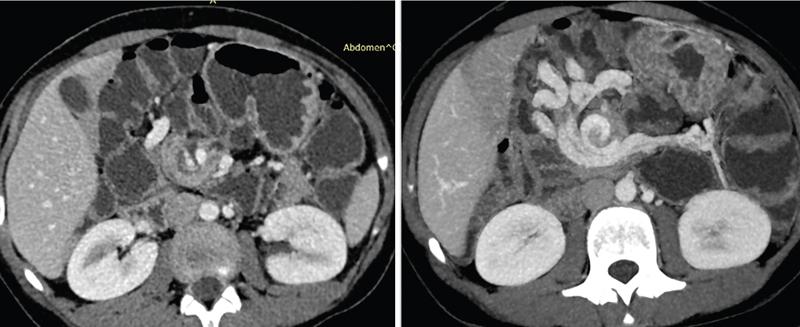

Computed tomography

CT enterography

CT enteroclysis